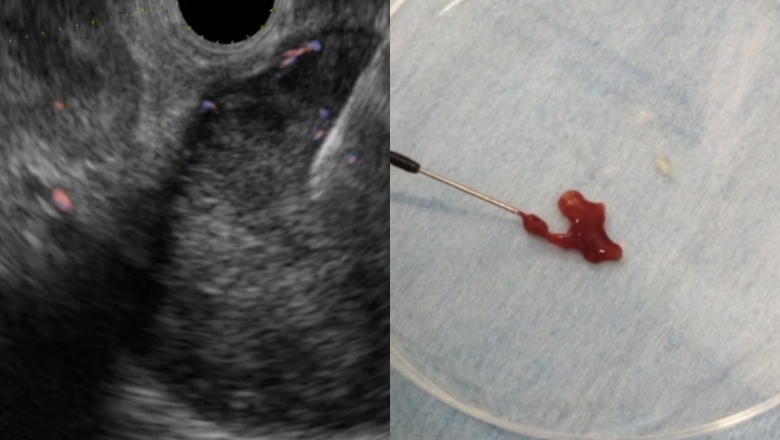

ERCP下腫瘍ラジオ波焼却術

超音波内視鏡を用いた診断・治療